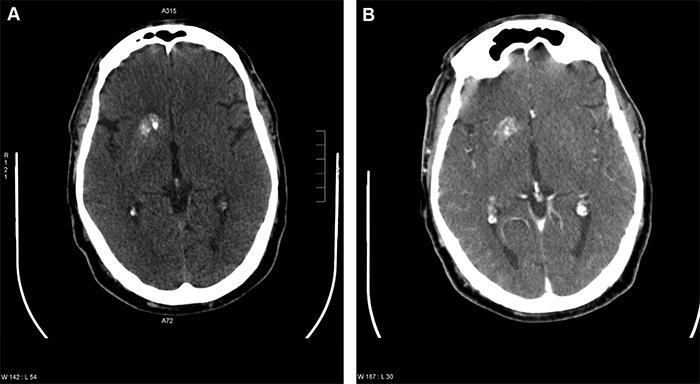

En la tomografía computada (TC) de cerebro, sin contraste, se observó mayor densidad a nivel del núcleo lenticular, especialmente del putamen, y de la porción posterior del núcleo caudado derecho. Se describen además, calcificaciones densas y heterogéneas en la cabeza del núcleo caudado y en la porción anterior del núcleo lenticular, que comprometen parcialmente el brazo anterior de la cápsula interna adyacente, sin efecto de masa significativo.

Al cumplir 10 días de evolución, con buen control metabólico, un nuevo TAC evidencia regresión parcial de la lesión lenticular descrita (Figura 1).